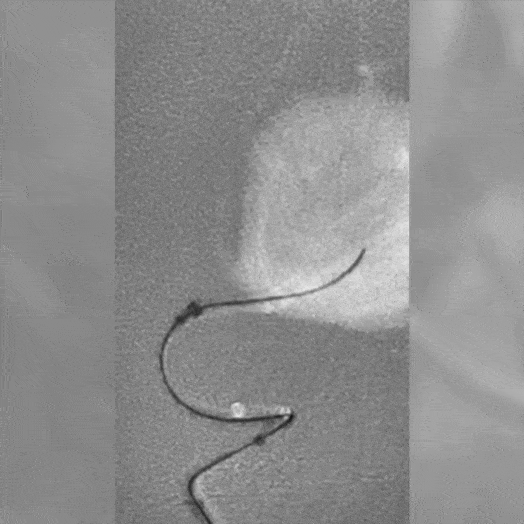

angiogram of embolization coils placed in a vessel

Proximal vessel sacrifice of LICA/LECA using POD400, PAC400, and PC400. A total of 877 cm of coil delivered by ACCESS25

Vessel Sacrifice

• POD400 + PAC400 for vessel sacrifice

• .020″ platform offered high volume and flexibility in case

• POD400 created a backstop, filled with PAC400

• BMX81 designed for stable vascular access